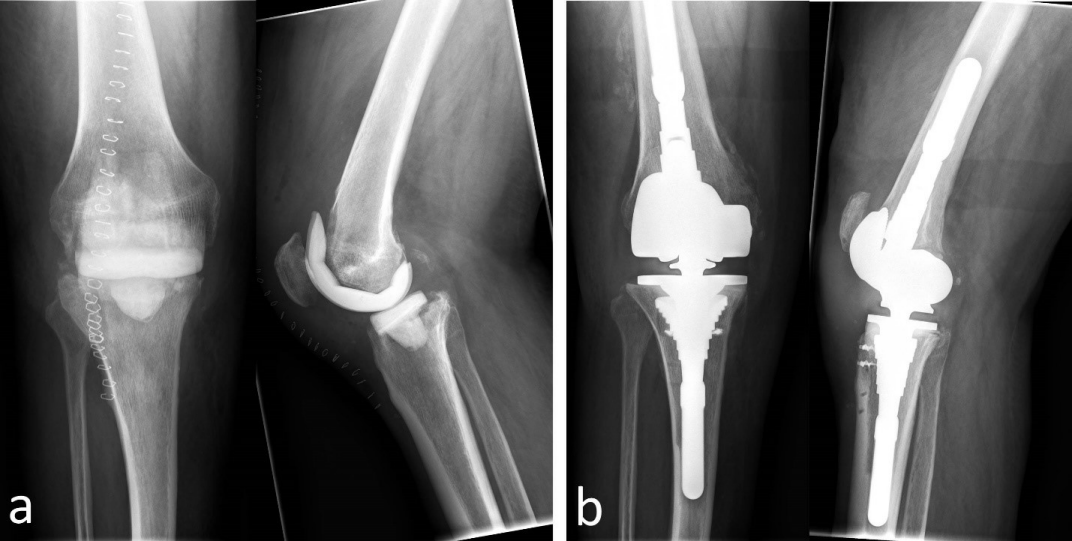

Surgical debridement and artificial joint explantation were carried out in all cases with temporary implantation of antibiotic containing cement spacer. In 85.7% (30) of the cases we used mobile spacers; in 14.3% (5) we introduced fixed spacers with intramedullary fixation (Figure 1 [Fig. 1] and Figure 2 [Fig. 2]). In those cases with mobile spacers we used the spacers produced by AGC Style Company Biomet Orthopedics Inc. Warsaw, USA. The system consists of a femoral shape size of 60 to 75 mm in 5 mm increments and a tibial mold size of 65 to 80 mm also available in 5 mm increments. Both are each filled with 80 g of cement and adapted to the local anatomy (Figure 1 [Fig. 1]). As intramedullary/fixed placeholder carbon or metal rods were intramedullary introduced and covered and surrounded with cement according to the defect size in the knee. In those cases we used Copal G+C Heraeus Medical GmbH (Wehrheim, Germany), each with 1 g of gentamicin and clindamycin applied to 40 g cement.

Figure 1: 62-year-old patient with TKR infection right. a) Radiograph of the knee anterior-posterior and lateral after implantation of a movable spacer (knee spacer AGC Style Company BiometOrthopedics Inc. Warsaw, U.S.A.). b) X-ray of knee anterior-posterior and lateral after re-implantation of revision-TKR (Typ LCS revision, Company DePuy Synthes, West Chester, PA, U.S.A.)